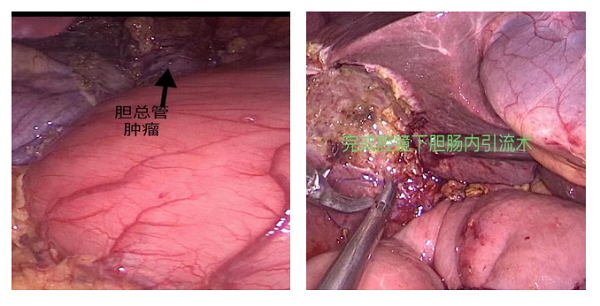

术中,见胆总管处肿物,质硬、浸润全层。首先探查腹腔无远处转移,在腹腔镜下游离胆总管下段,将胆总管切缘送术中快速冰冻,结果为:阴性,遂决定行腹腔镜胆管癌根治术。